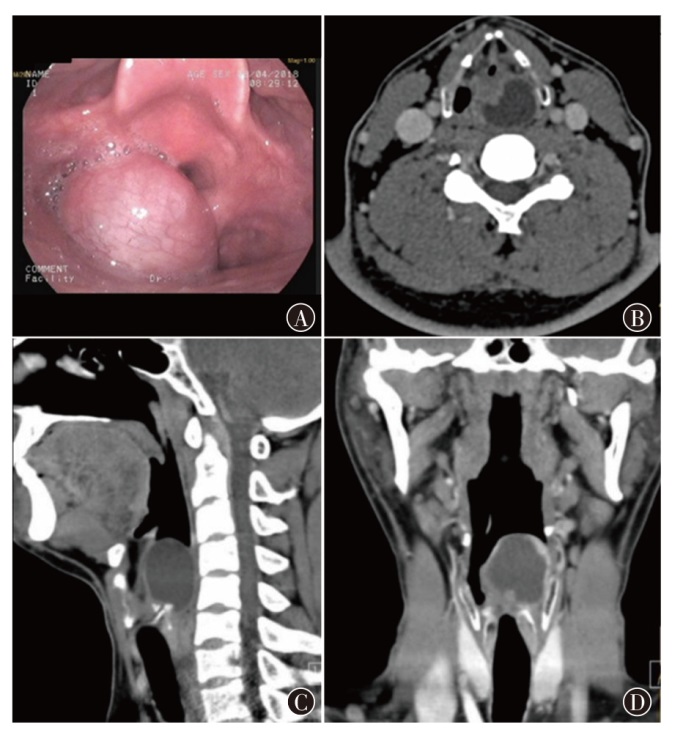

治疗头颈部软组织肉瘤对于完整切除和功能保护有较高的挑战。现报道1例声门上区喉滑膜肉瘤患者的诊疗经过,并就相关文献进行复习,以提高对该类疾病的认识。